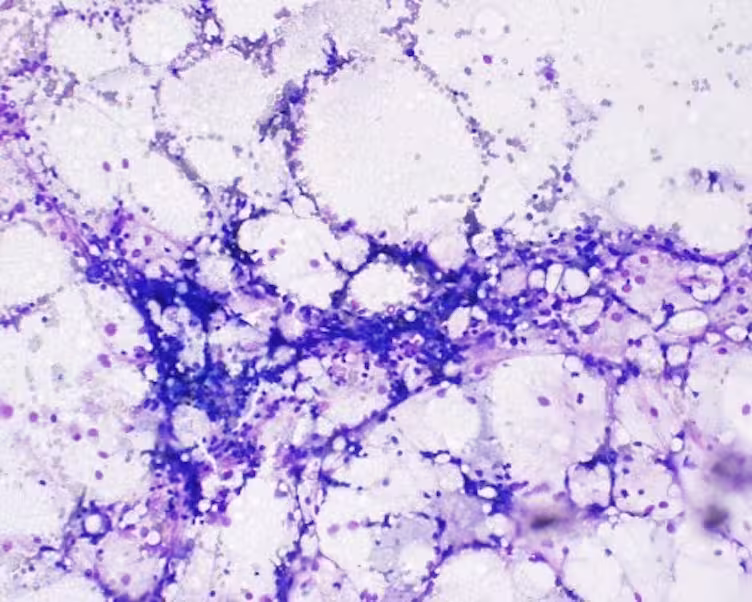

.avif)